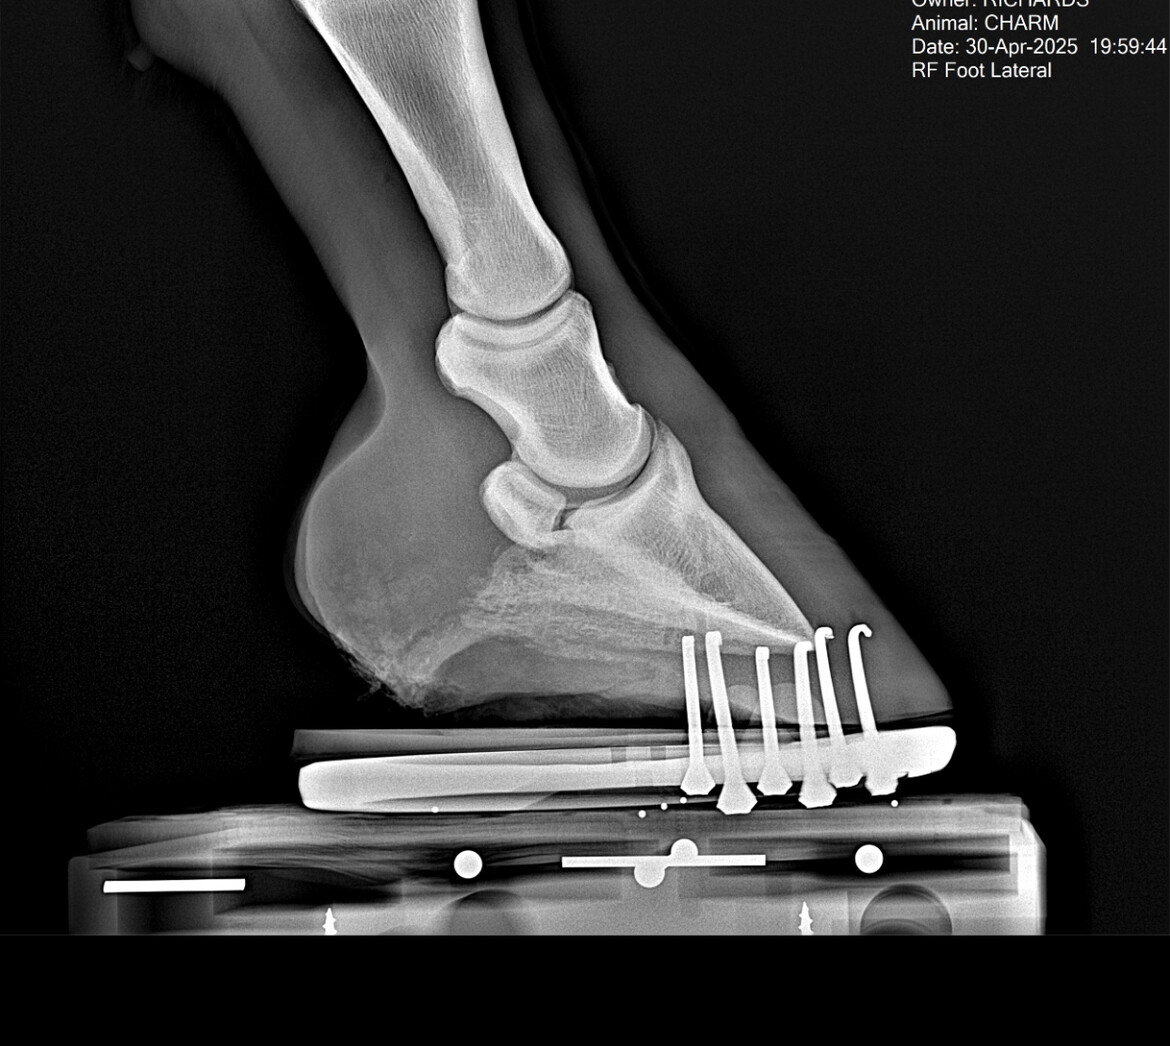

Vetrinary x-rays from April 2025 confirm Charm’s Navicular diagnosis (images are in the photos for viewing). These images also stand to confirm ‘why’ retirement to a healing sanctuary is the most compassionate option for Charm.

Updated: $2500 was given as a Trust with Faith Deposit, along with $350. To secure Charms transition to the Sanctuary for Retirement. The Farrier who is also an instructor for barefoot care, has reviewed Charms Xray and will be taking his heart bar "work shoes" off Wednesday and part of his long term holistic care program to help heal Charms Navicular Injury. Continue reading for full details and thank you for your contributions that help this deserving horse retire and get the holistic care, time and freedom, he needs...to heal.